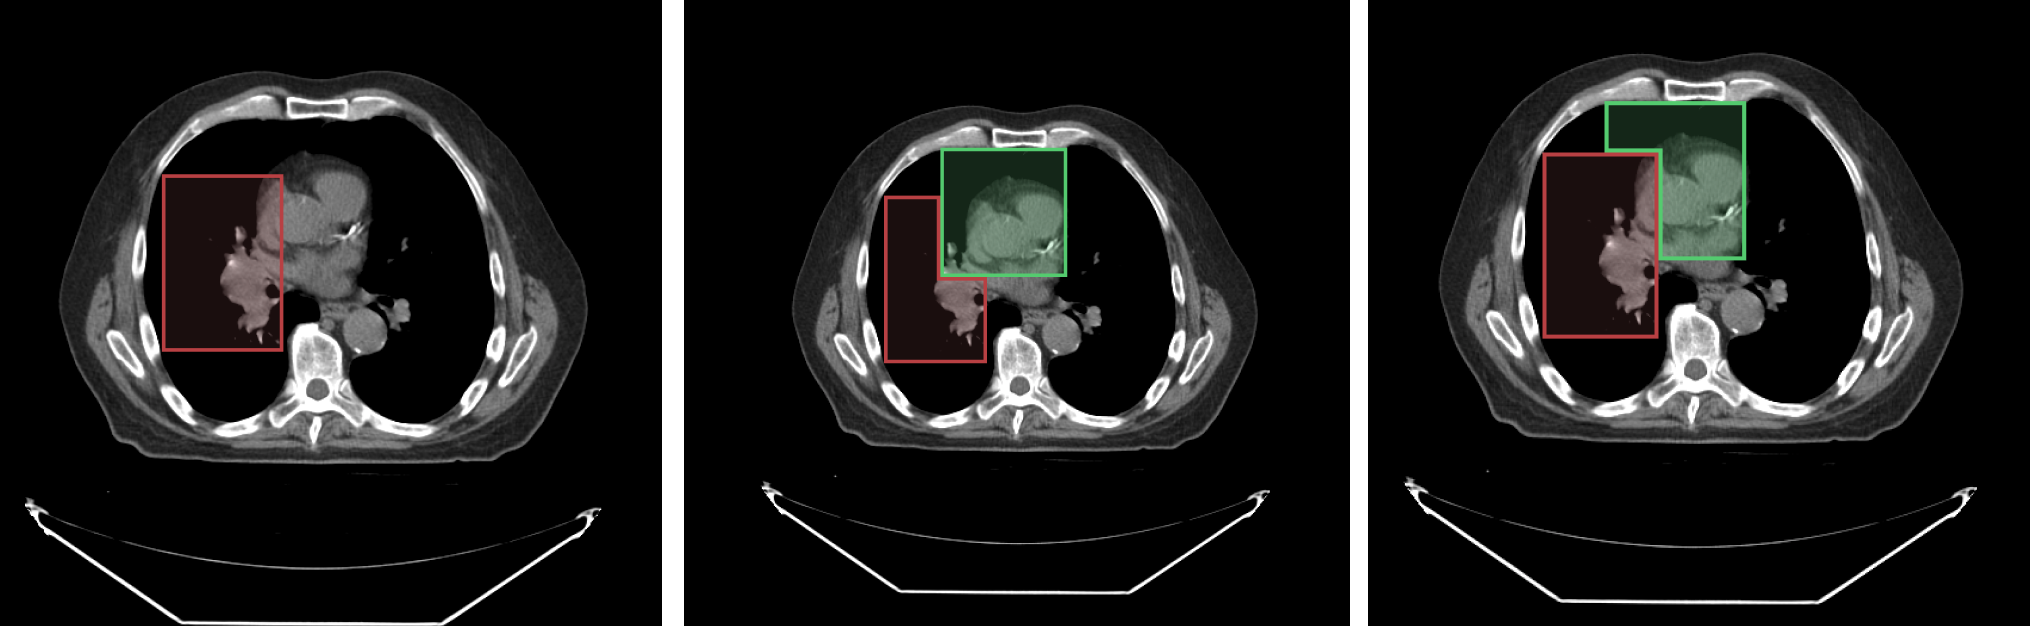

To give an example consider the following image with an overlaid labelmap.

The left image shows segment index 1, the middle image shows the result when segment index 2

is drawn on top of segment index 1, and the right image shows the result when segment index 1

is locked and segment index 2 is drawn on top of segment index 1.

As you see in the locked scenario (right image), the segment index 1 cannot be changed by the new drwaing.